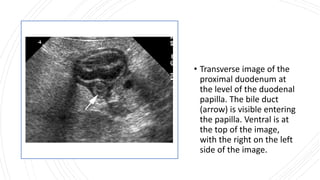

• Transverse image of the

proximal duodenum at

the level of the duodenal

papilla. The bile duct

(arrow) is visible entering

the papilla. Ventral is at

the top of the image,

with the right on the left

side of the image.

• Transverse imageof the proximal duodenum at the level of the duodenal papilla. The bile duct (arrow) is visible entering the papilla. Ventral is at the top of the image, with the right on the left side of the image.